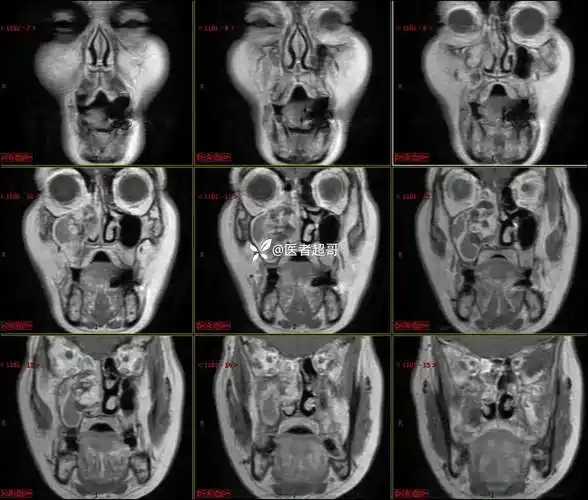

感冒引起闭塞,继发鼻腔出血,太阳穴周胀痛就诊,ct,mri齐全请分析!